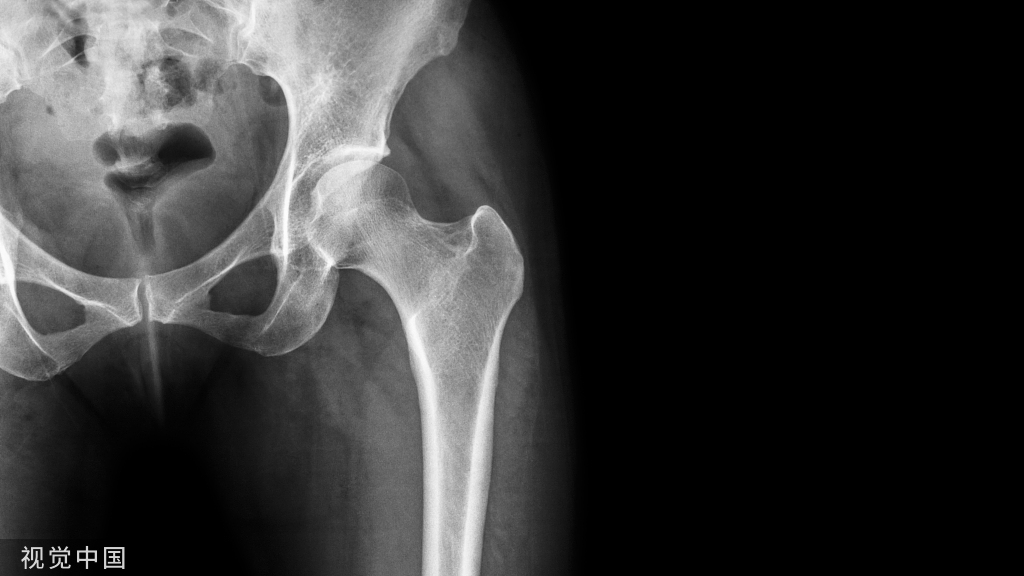

⑧ 复位后典型病例图。